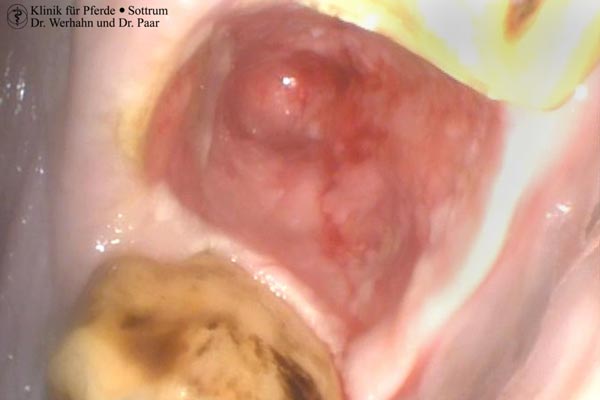

Eine weit verbreitete Erkrankung der Schneidezähne stellt die EOTRH (Equine Odontoclastic Tooth Resorption and Hypercementosis) dar. Diese Erkrankung ist geprägt durch die Auflösung von Zahnsubstanz, Zunahme an Zahnzement unter Verlust des Zahnhalteapparates und geht mit teilweise erheblichen Schmerzen einher. Die Untersuchung umfasst die klinische und röntgenologische Untersuchung. Durch intraorale Röntgenverfahren werden die Ober- und Unterkieferschneidezähne isoliert dargestellt und das gesamte Ausmaß der Erkrankung wird sichtbar. In Einzelfällen sind auch die Hengst- und sogar Backenzähne betroffen. Es handelt sich um eine progressiv fortschreitende Erkrankung, bei der letztlich oftmals nur die Entfernung der erkrankten Zähne Abhilfe schafft und für Schmerzfreiheit sorgt. Zahnfleisch ist ein wunderbares Gewebe und das einzige im Körper was narbenfrei abheilt. Dies ist die Grundlage dafür, dass nach durchgeführter Entfernung der Schneidezähne die ehemaligen Zahnfächer gut und schnell abheilen und nur wenige Wochen später die zunächst tiefen Wunden vollständig ausgeheilt sind. Viele Besitzer berichten davon wie sich Ihre Pferde nach Entfernung der erkrankten Schneidezähne deutlich positiv im Verhalten ändern: Der chronische „Zahnschmerz“ ist endlich überstanden.